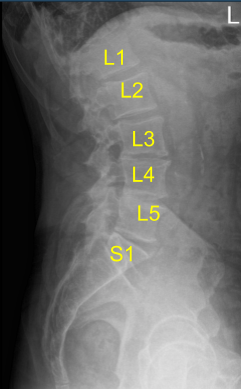

A spinal needle was inserted into a presumed L2 vertebral body. C-arm was brought in and lateral views were taken and confirmed that the needle was at L2 pedicle. Skin incision was marked and the skin was incised using a #10 blade. Using Bovie a deep dissection was performed through the deep fascia and on the right side of the spinous process of L2 and L3.

The lamina of L2 and L3 were exposed up to the medial facet joint. Once hemostasis was achieved, the Woodson was inserted in the L2-3 disc space and C-arm was brought in for a lateral view. The level of L2-3 was re-confirmed and saved.